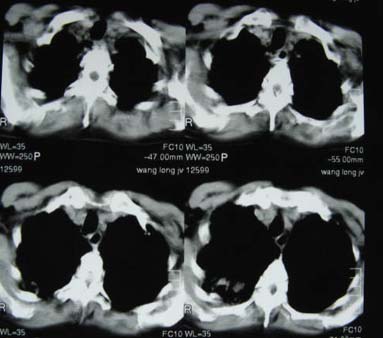

考虑为wg肉牙肿

肺转移瘤,肺泡细胞癌,播散性肺结核都有可能的.说不好还是金葡菌感染呢